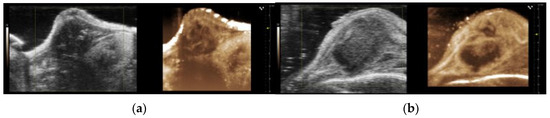

The B-mode ultrasound images of the orthotopic and subcutaneous tumours are presented in Figure 2a,b. Additional images are presented in Supplementary Figure S2. The orthotopic tumours were primarily localised within the pancreas. However, a prominent protrusion often infiltrated and extended outside the abdominal wall (Figure 2a). This could have resulted from the needle leaking tumour cells as it was retracted from the pancreas during implantation. Additionally, potential damage to the peritoneal wall and surrounding tissue during the surgical procedure may have facilitated tumour growth, forming the protrusion.

Figure 2. Representative B-mode images and regions of interest (ROI) of the orthotopic (a) and subcutaneous (b) KPC tumours. Growth curves of the orthotopic and subcutaneous KPC tumours (c). Tumour volume 14 days after implantation (d). Each dot represents one tumour. The error bars indicate the SD. The asterisks indicate a statistically significant difference evaluated by a two-tailed t-test. (** p < 0.005). The sample size was n = 5 for the orthotopic tumours and n = 10 for the subcutaneous group.

In terms of the infiltration and metastatic sites, the orthotopic tumours presented infiltration to neighbouring tissues and were metastasised into several organs: the spleen, intestines, kidneys, and liver, as summarised in Table 1. The subcutaneous tumours presented infiltration into the adjacent muscle tissue, and no metastases were found. Comparing the tumour growth revealed that the orthotopic tumours reached larger volumes, particularly during the final five days of the study period (Figure 2c). Fourteen days after implantation, the orthotopic tumours had an average volume that was two times larger than the subcutaneous tumours (Figure 2d). The final volume of the subcutaneous tumours presented less variability than the orthotopic tumours.